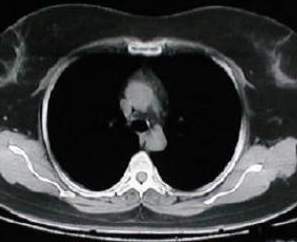

Radiografía del tórax

Tomografía torácica